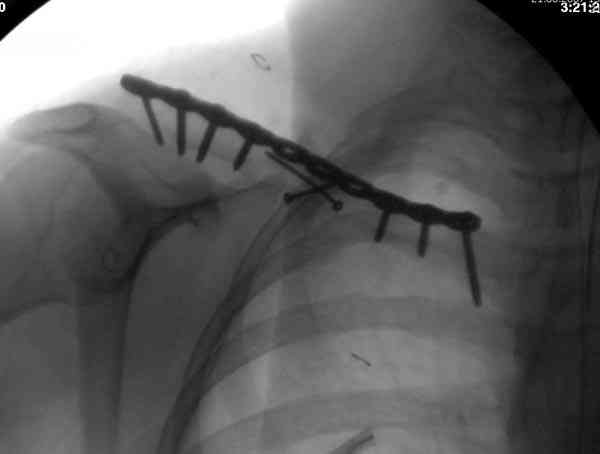

Консервативное лечение, через 8 мес. операция Rockwood pin с костной пластикой в нашем городе другим врачом. После 8 недели падение, гвоздь удален оперирующим хирургом, больная направлена к нам. Фиксация реконструктивной пластиной с трикортикальным графтом, добавлен BMP-2. Для стабилизации фиксацию провели через акромион.

Вот уже два месяца больная также продолжает жаловаться на боли, буквально на днях удалили акромиальную часть пластины с специальной пилой с алмазным покрытием для медицинского металла. До сих пор судьба ложного сустава неизвестна....